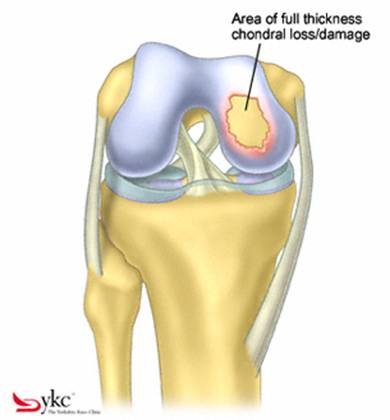

Fig.21. Diagrama unei leziuni cartilaginoase.

Chirurgul trebuie sa fie foarte atent atunci cand examineaza posteriorul condililor femurali. Daca se semnaleaza orice vatamare/rana/deteriorare pe suprafetele articulare, trebuie sa se cerceteze atent calitatea cartilagiului. Orice flapsuri instabile sunt inlaturate prin folosirea unui aparat de ras electric artroscopic sau curette. Apoi, un curette este folosit pentru a debrida stratul de cartilagiu calcifiat de la baza in toata grosimea defectului. Acest pas se bazeaza pe activitatea lui Frisbi, care a demonstrat vindecarea suprafetei articulare superioare la un cal, cand stratul cartilagiului calcifiat este indepartat. Cand indepartam stratul cartilagiului calcifiat, in general nu se foloseste un aparat de ras. Cu un aparat de ras este dificil de controlat cantitatea de os eliminat, si este posibil ca osul subcondral sa fie afectat.